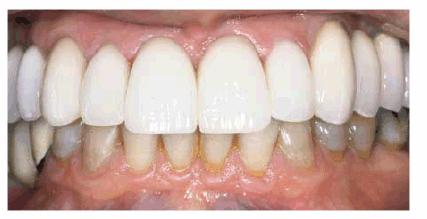

Figures 29-12A to C show a 75-year-old woman who presented

with severe root caries and moderate periodontal disease. Her daughter, who

disclosed that her mother was difficult to please, referred her. The daughter

was very supportive of her mother receiving dental treatment; however, her

mother was initially not interested. The mother did not think that the esthetic

aspect of dentistry was important. During consultation with the dentist, the

mother was informed of the infection in her mouth and the potential effect that

this could have on her future health and functionality. The patient consented

to have the maxillary arch restored with fixed prosthodontics. She refused to

accept treatment for her mandibular teeth, preferring to use her existing

partial denture. Figures 29-12D, and 29-12E show the final result after periodontal and

prosthodontic treatment. Although the patient was not particularly grateful to

have the dental treatment, her family was thrilled to have the caries infection

removed and the esthetic appearance improved. The patient lived with her

esthetically improved appearance for an additional 13 years.

Figure 29-12A to C: This 75-year-old woman had severe root caries and moderate periodontal disease.

Figure 29-12D: Although this woman stated that she would "just as soon have her teeth extracted," she was motivated to have both periodontal and prosthodontic treatment.

Figure 29-12E: The patient's smile after esthetic dental treatment shows just how much she appreciated her dental treatment.